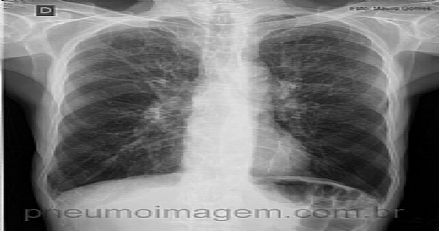

APROVADA PELA ANVISA NOVA DROGA PARA DPOC NO BRASILAprovado pela ANVISA o Brometo de Glicopirrônio na última semana, nova droga anticolinérgica de ação prolongada para uso em DPOC no Brasil, produzida pela Novartis. A nova droga deve ser comercializada com o nome comercial "Seebri" em cápsulas contendo pó para uso inalatório.

Veja imagens sobre DPOC no PneumoImagem, clique aqui.